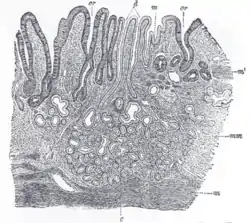

![]() Section of duodenum of cat. X 60. (Muscularis mucosae labeled at right, third from the top.) | |

The muscularis mucosae is composed of several thin layers of smooth muscle fibers oriented in different ways which keep the mucosal surface and underlying glands in a constant state of gentle agitation to expel contents of glandular crypts and enhance contact between epithelium and the contents of the lumen.